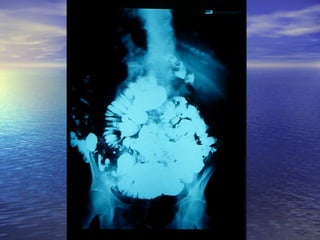

• Estudio radiológico consiste enEstudio radiológico consiste en

administración de 250ml oral de bario y laadministración de 250ml oral de bario y la

obtención de radiografías seriadas delobtención de radiografías seriadas del

intestino, realizadas a intervalos, hastaintestino, realizadas a intervalos, hasta

que el contraste llega al cielo.que el contraste llega al cielo.

Parámetros para analizarParámetros para analizar

• 1.- Calibre de la luz intestinal1.- Calibre de la luz intestinal

• 2.- Contornos Superficie de mucosa2.- Contornos Superficie de mucosa

• 3.- Grosor de la pared de la mucosa3.- Grosor de la pared de la mucosa

• 4.- Desplazamiento de asas4.- Desplazamiento de asas

• 5.- Floculación, segmentación,5.- Floculación, segmentación,

obstrucciónobstrucción (Yeyuno imagen = pluma de(Yeyuno imagen = pluma de

aves)aves)

(ileon imagen = pila de monedas)(ileon imagen = pila de monedas)